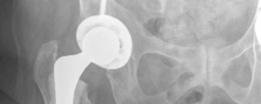

Given the patient's age and the presence of proximal femoral osteopenia (Dorr Type B/C bone morphology), templating was directed toward a hybrid total hip arthroplasty construct. This involves an uncemented, press-fit acetabular component and a cemented femoral stem. The templating confirmed that a standard offset cemented stem would adequately restore the patient's native biomechanics.

The Rationale for a Hybrid Construct

The term "Hybrid Primary Hip Arthroplasty" refers to the use of an uncemented (press-fit) acetabular component combined with a cemented femoral stem.

- Uncemented Acetabular Component: In the absence of severe acetabular osteoporosis or prior radiation, uncemented cups provide excellent long-term biologic fixation. They allow for the use of highly cross-linked polyethylene liners and larger femoral heads, which optimize the head-to-neck ratio and maximize the jump distance, thereby reducing the risk of postoperative dislocation.

Therefore, a hybrid construct offers the optimal balance: minimizing the risk of periprosthetic femoral fracture while maximizing the longevity and stability of the acetabular reconstruction.

Once the appropriate size was reached, a highly porous, titanium-coated hemispherical cup was impacted into place. The target orientation was 40-45 degrees of inclination and 15-20 degrees of anteversion. Excellent primary stability was achieved via the equatorial press-fit. Two cancellous screws were placed in the postero-superior quadrant (the safe zone) to augment initial fixation. A highly cross-linked polyethylene liner was then impacted into the shell.